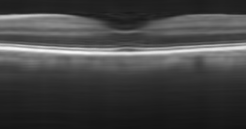

The effect of the overlap of the patches on the final output of the algorithm has been investigated in the next simulation. For this purpose, the outputs of the proposed approach for the situations and have been compared. When , the patches have no overlap. The resulting higher resolution OCT images for each situation have been illustrated in Fig. 8. Visual comparison in addition to the PSNR and SSIM for each image, show that using patches with overlap, we can increase the performance of the algorithm and consequently improve the quality of the output image.

Reference image

Using patches without overlap

Using patches with overlap